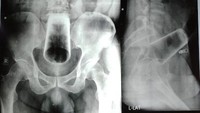

Pria berusia 56 di Nepal datang ke unit gawat darurat rumah sakit setelah memasukkan botol kaleng bekas ke dalam anusnya, 6 pekan sebelum ke dokter. Ia mengalami tinja keras, muntah, dan sakit perut. (Foto: International Journal of Surgery Case Reports)